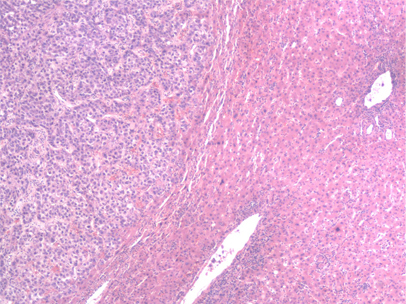

Medium power microscopic view of a hematoxylin and eosin stained section depicting normal liver on the right and HCC on the left. A sharp boundary separates the distinct zones of normal liver and tumor

From the personal collection of Badar Muneer MD, Florida Hospital Transplant Center, Orlando, FL; used with permission